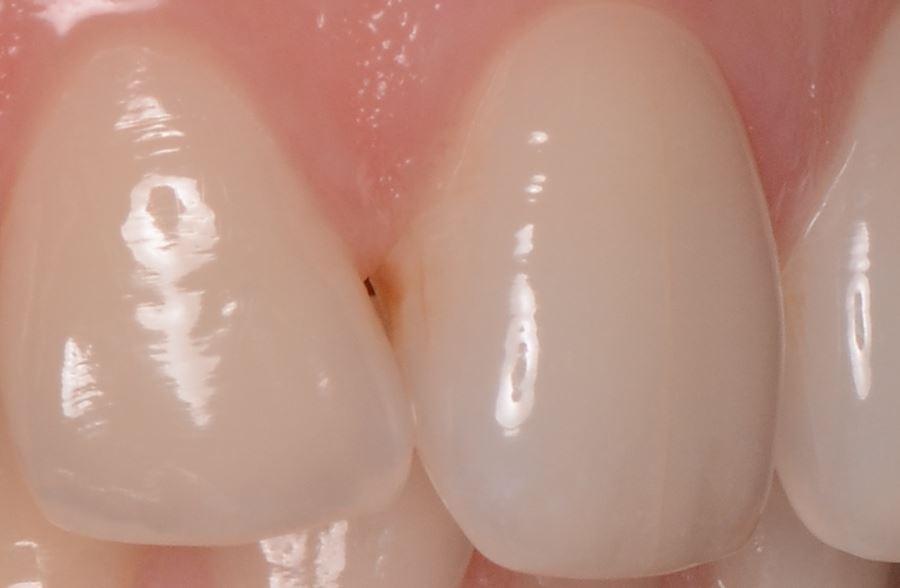

На эмали есть небольшое пятнышко после лечения Icon месяца 2 назад (пятно посветлело, но полностью не ушло).

До лечения Icon пятно выглядело так (было гладким, не шершавым), после лечения нет в хорошем качестве, но пятно светлее.